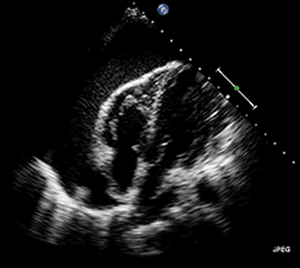

| A 2D transthoracic Echocardiogram of pericardial effusion. The Swinging Heart | |

Pericardial effusion ("fluid around the heart") is an abnormal accumulation of fluid in the pericardial cavity. Because of the limited amount of space in the pericardial cavity, fluid accumulation leads to an increased intrapericardial pressure which can negatively affect heart function. A pericardial effusion with enough pressure to adversely affect heart function is called cardiac tamponade. Pericardial effusion usually results from a disturbed equilibrium between the production and re-absorption of pericardial fluid, or from a structural abnormality that allows fluid to enter the pericardial cavity.